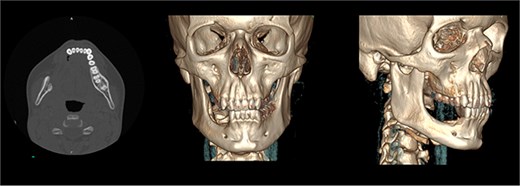

The patient was admitted from the clinic for urgent evaluation. Routine blood investigations were normal. An orthopantomogram revealed displacement of the second and third molars and a poorly defined superior margin of the alveolar process, suggesting osseous involvement (Fig. 2). Contrast-enhanced computed tomography (CT) of the facial bones and neck demonstrated a well-defined lucent lesion within the mandibular body with exophytic soft tissue extension into the oral cavity (Fig. 3). Magnetic resonance imaging (MRI) of the neck illustrated the hyperintense soft-tissue component with no rim enhancement or necrosis (Fig. 4). There was no lymphadenopathy noted clinically or radiograpgically.

CT showing well defined lucent lesion within the body of the right side of the mandible with exophytic soft tissue component extending into oral cavity.